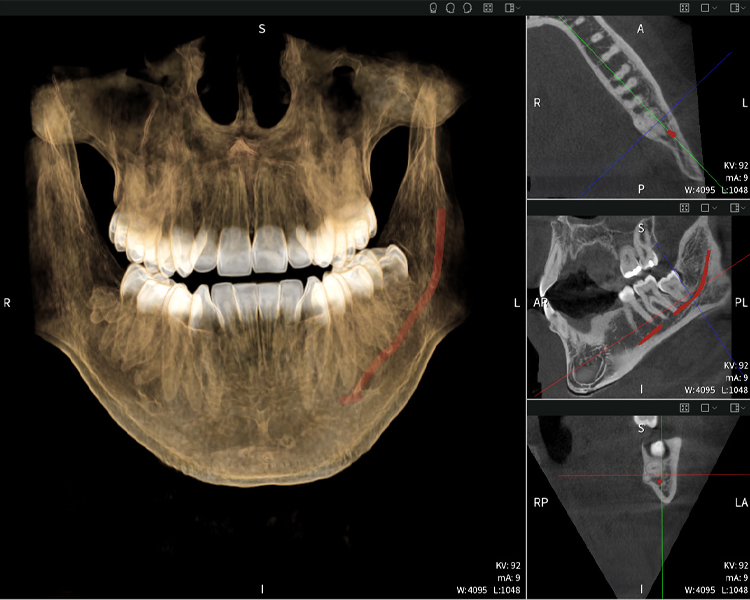

Abbildung d: Bildgebungsergebnisse von Seethrough Max vor einem schwarzen Hintergrund.

Abbildung d

Abbildungen b–d zeigen verschiedene Ansichten einer 3D-Rekonstruktion des Unterkiefers und bieten eine umfassende Übersicht über die Anatomie des Unterkiefers, die Lage der Nerven im Verhältnis zu den Zähnen und ermöglichen die Beurteilung der Zahnsymmetrie und Ausrichtung.

Abbildung d zeigt den bereits vorbehandelte Zahn 48, dessen Krone entfernt wurde und dessen Wurzeln nahe am Nerv belassen wurden, was das hohe Risiko einer Nervenschädigung verdeutlicht.